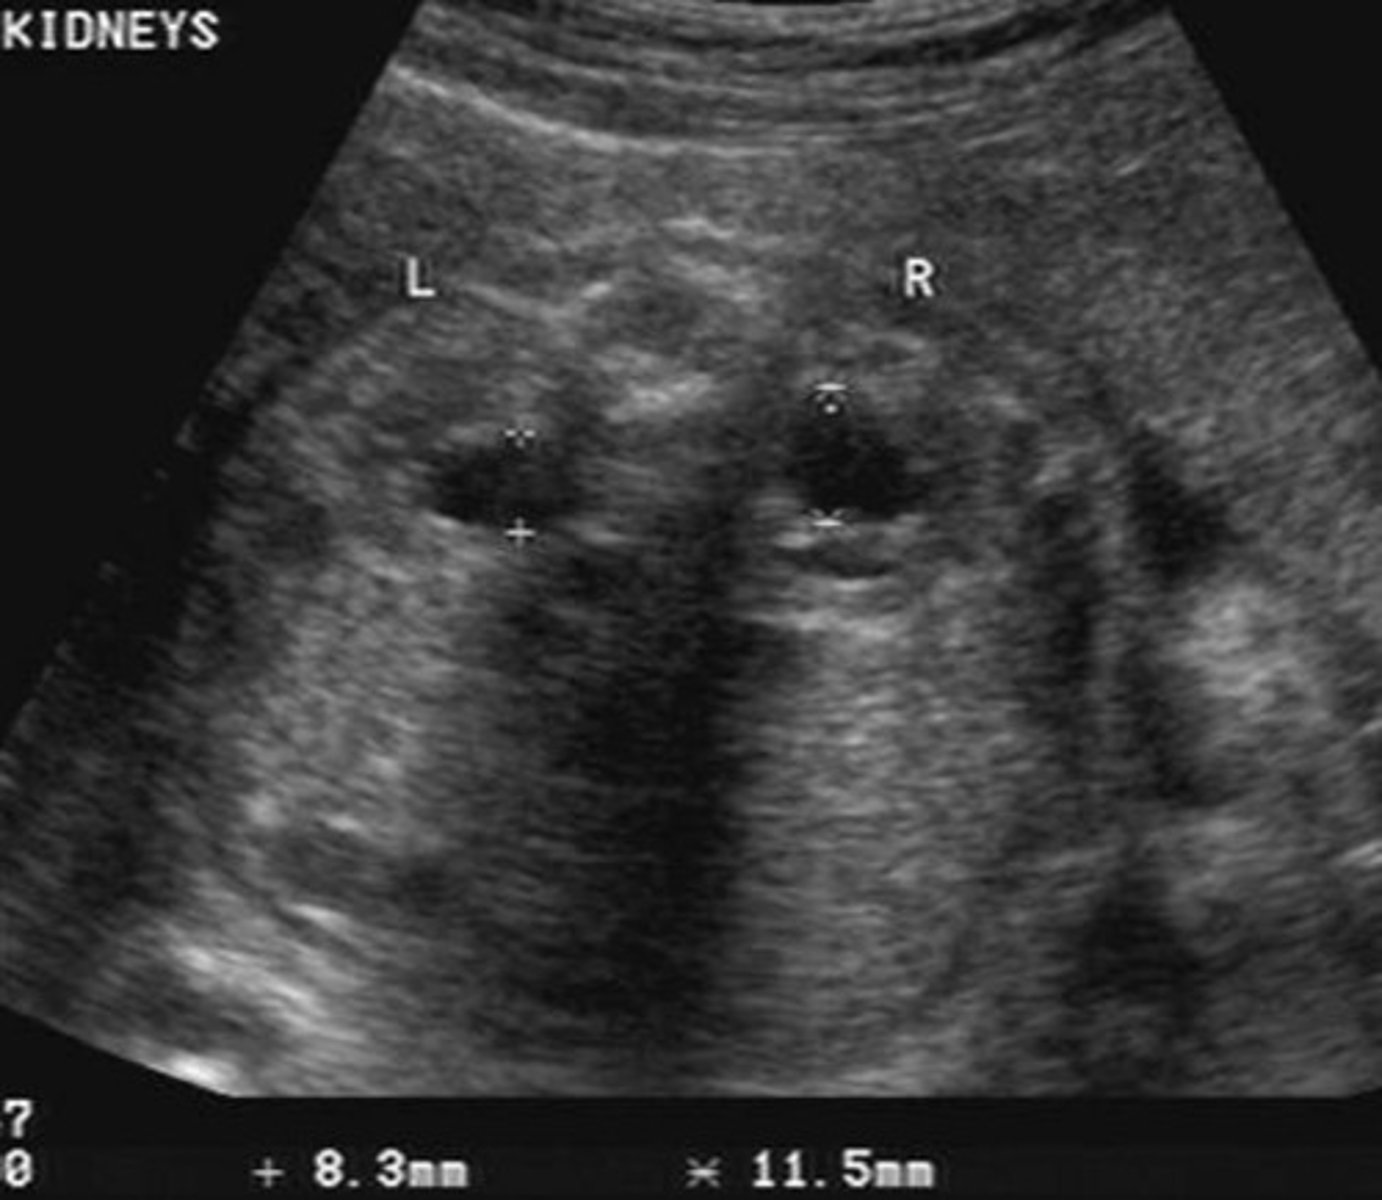

Potter's Syndrome Type II - Multicystic Dysplastic Kidney Disease

Kidney tissue is replaced by cysts - multiple and variable in size

Usually unilateral

Enlarged kidneys

Ill-defined walls & parenchyma/pelvis